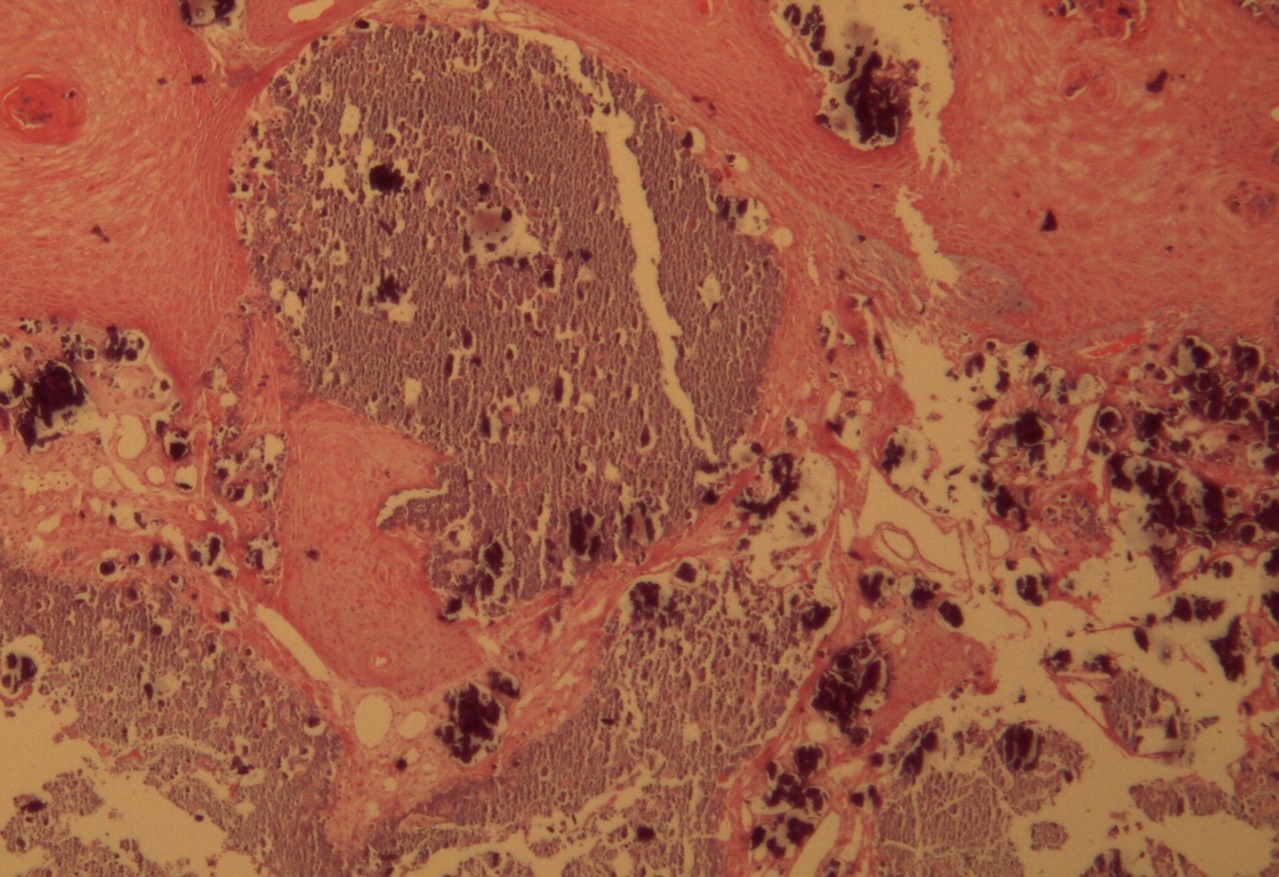

Figure 1.Hyperkeratosis, hypergranulosis, proliferation of dermal vessels, and surface and deep calcium deposits. HE. 100x.

Figure 2.Common wart with calcium foci at the level of the dermal vessels grouped in lobules. HE. 200x.

Figure 3.Relationship of calcium foci in the papillary dermis with the overlying epidermal hyperplasia. HE. 200x.

A 9-year-old male patient who was treated in the dermatology service for a progressively growing keratotic nummular dermal lesion on the right knee. With the clinical judgment of viral wart, the lesion was removed. In the Pathology Service, a nummular keratotic lesion of 0.5 cm in maximum dimensions was received, which crackled when cut. Figure 1, Figure 2, Figure 3, Figure 4, Figure 5